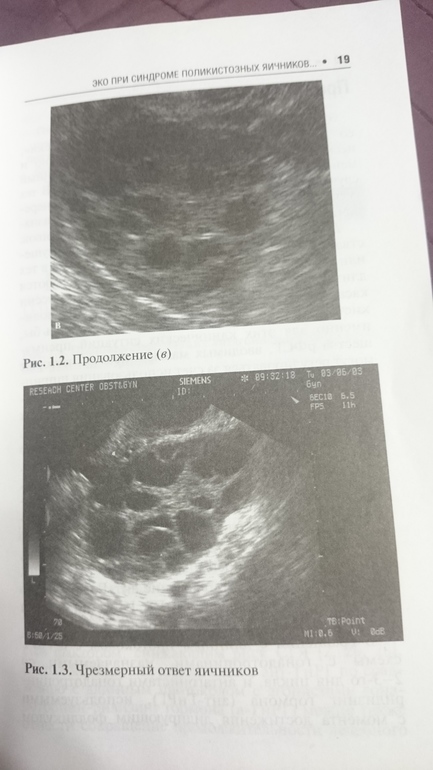

И почему они пишут, что чрезмерный ответ яичников? На фото

По моему шикарный)

В узи не особо разбираюсь, все-таки фотка плоская, а не объемная, если учесть, что такая картинка не с одной, а со всех сторон, наверное, чрезмерный. В любом случае, классическим ответом считается по 5-7 фолликулов в яичнике, а при спкя сама знаешь, обычно больше, причем на низких дозах, хотя обычные женщины свои 5-7 (10-15) получают на дозах 200-300.